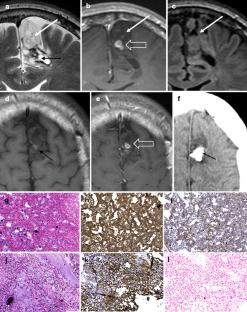

From a total of 61 DNTs, 48 simple and 13 complex variants were identified. Multiple or single pseudocysts in a cortical/subcortical location with small cysts sometimes separated from the tumor represented the glioneuronal element and were found in all DNTs. FLAIR hyperintense tissue was found between pseudocysts but—in neocortical DNTs—also circumscript in deeper tumor parts. Calcification and hemorrhages in this location occurred in four of 13 complex variants, and one of these patients was also the only one with tumor growth. Patients with complex variants had earlier seizure onset, and complex variants were more often located outside the temporal lobe. Although complex variants represented a higher diagnostic challenge, misdiagnoses also occurred in simple variants. One of five of DNTs showed contrast enhancement, which varied on follow-up studies with enhancing parts becoming nonenhancing and vice versa.

The glioneuronal element is readily identifiable on MRI and should be considered to support the DNT diagnosis. Complex DNT variants have a different clinical profile and a more variable histopathological and MRI appearance; however, misdiagnoses occasionally also occur in simple variants.